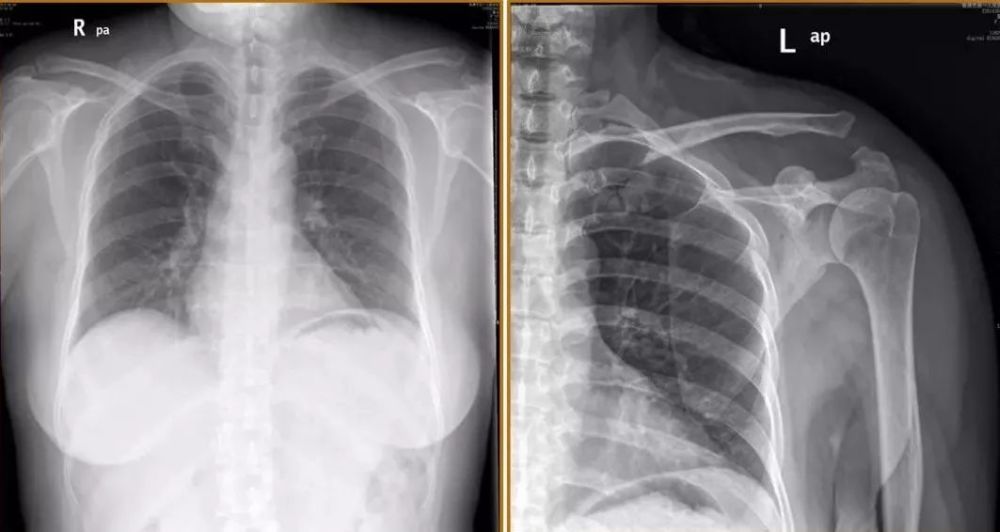

伤肩x光片

外伤患者左锁骨骨折的肩部x光片

左肩关节诸骨皮质连续,形态规整,左侧肩锁关节间隙较宽,软组织影未见

右锁骨中段骨折